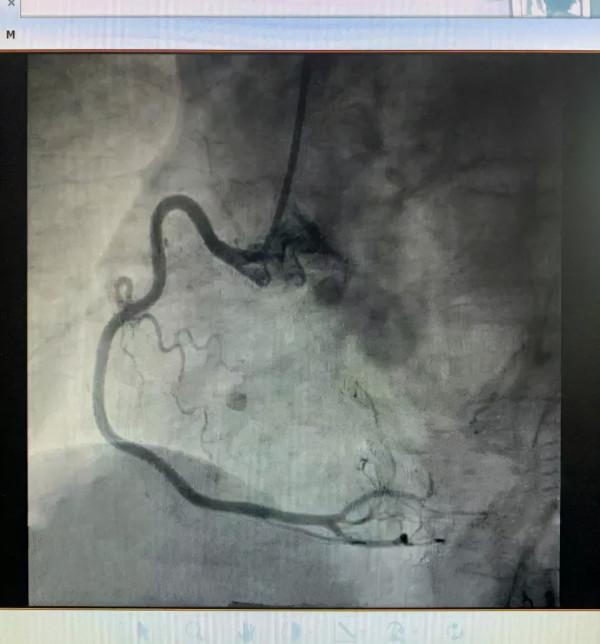

手術當天,所有術前準備工作就緒,陳曉麗副主任醫師和楊祖芳醫師,順利建立鎖骨下靜脈,股動脈和股靜脈通路,完成冠狀動脈造影,繼而放置電生理電極,經電生理檢查證實為慢--慢型房室結折返性心動過速(AVNRT),這是一種不典型的雙徑路,這種型別在PSVT裡也不多見,在三維標測系統指引下,心內科學科帶頭人王健主任醫師帶領團隊順利完成了這例室上速的射頻消融術。

冠脈造影排除冠心病,射頻消融術治癒心律失常,超聲心動圖提示左心室肥厚,這種改變多數是來自長期控制不良的高血壓,這就很好地解釋了患者心電圖ST段壓低。